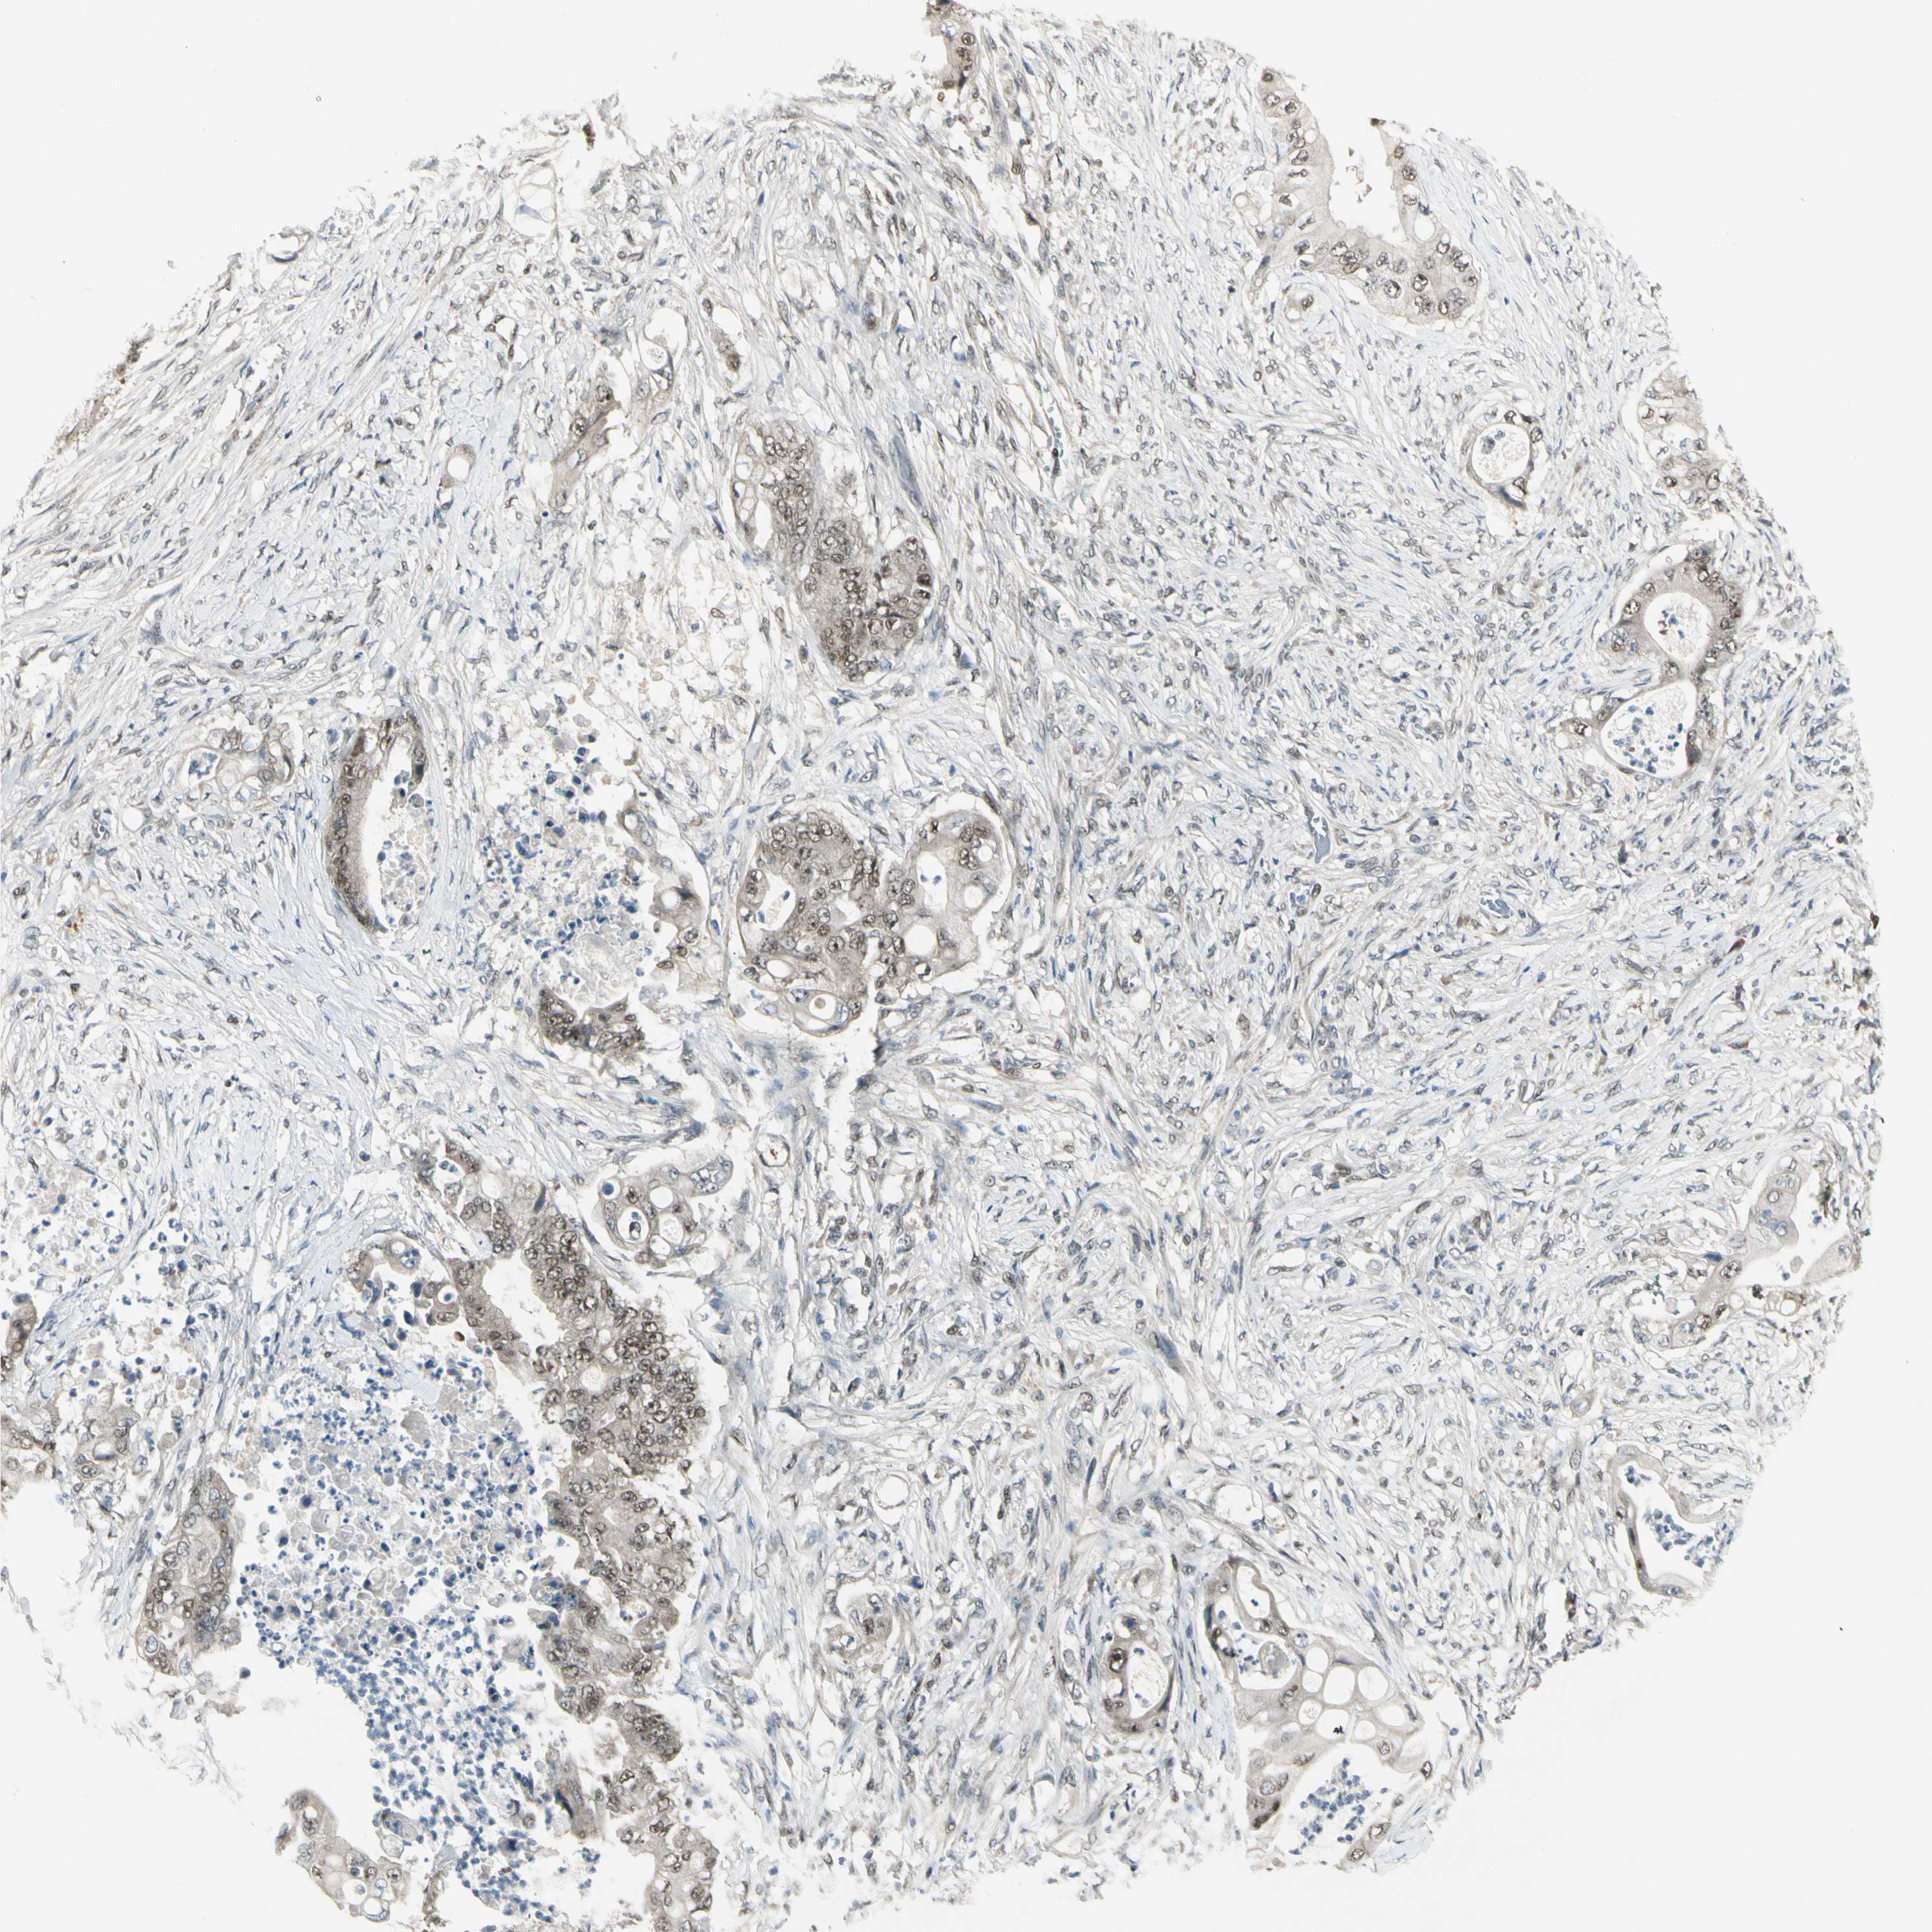

STOMACH CANCER - Protein expressioni

A mouse-over function shows sample information and annotation data. Click on an image to view it in a full screen mode. Samples can be filtered based on level of antibody staining by selecting one or several of the following categories: high, medium, low and not detected. The assay and annotation is described here.

Note that samples used for immunohistochemistry by the Human Protein Atlas do not correspond to samples in the TCGA dataset.

Antibody stainingi

Antibody staining in the annotated cell types in the current human tissue is reported as not detected, low, medium, or high, based on conventional immunohistochemistry profiling in selected tissues. This score is based on the combination of the staining intensity and fraction of stained cells.

Each image is clickable and will lead to virtual microscopy that enables deeper exploration of all samples and also displays staining intensity scores, fraction scores and subcellular localization as well as patient and tissue information for each sample.

Antibody HPA007990

Staining

High

Medium

Low

Not detected

Intensity

Strong

Moderate

Weak

Negative

Quantity

>75%

75%-25%

<25%

None

Location

Nuclear

Cytoplasmic/membranous

Cytoplasmic/membranous,nuclear

Adenocarcinoma, NOS